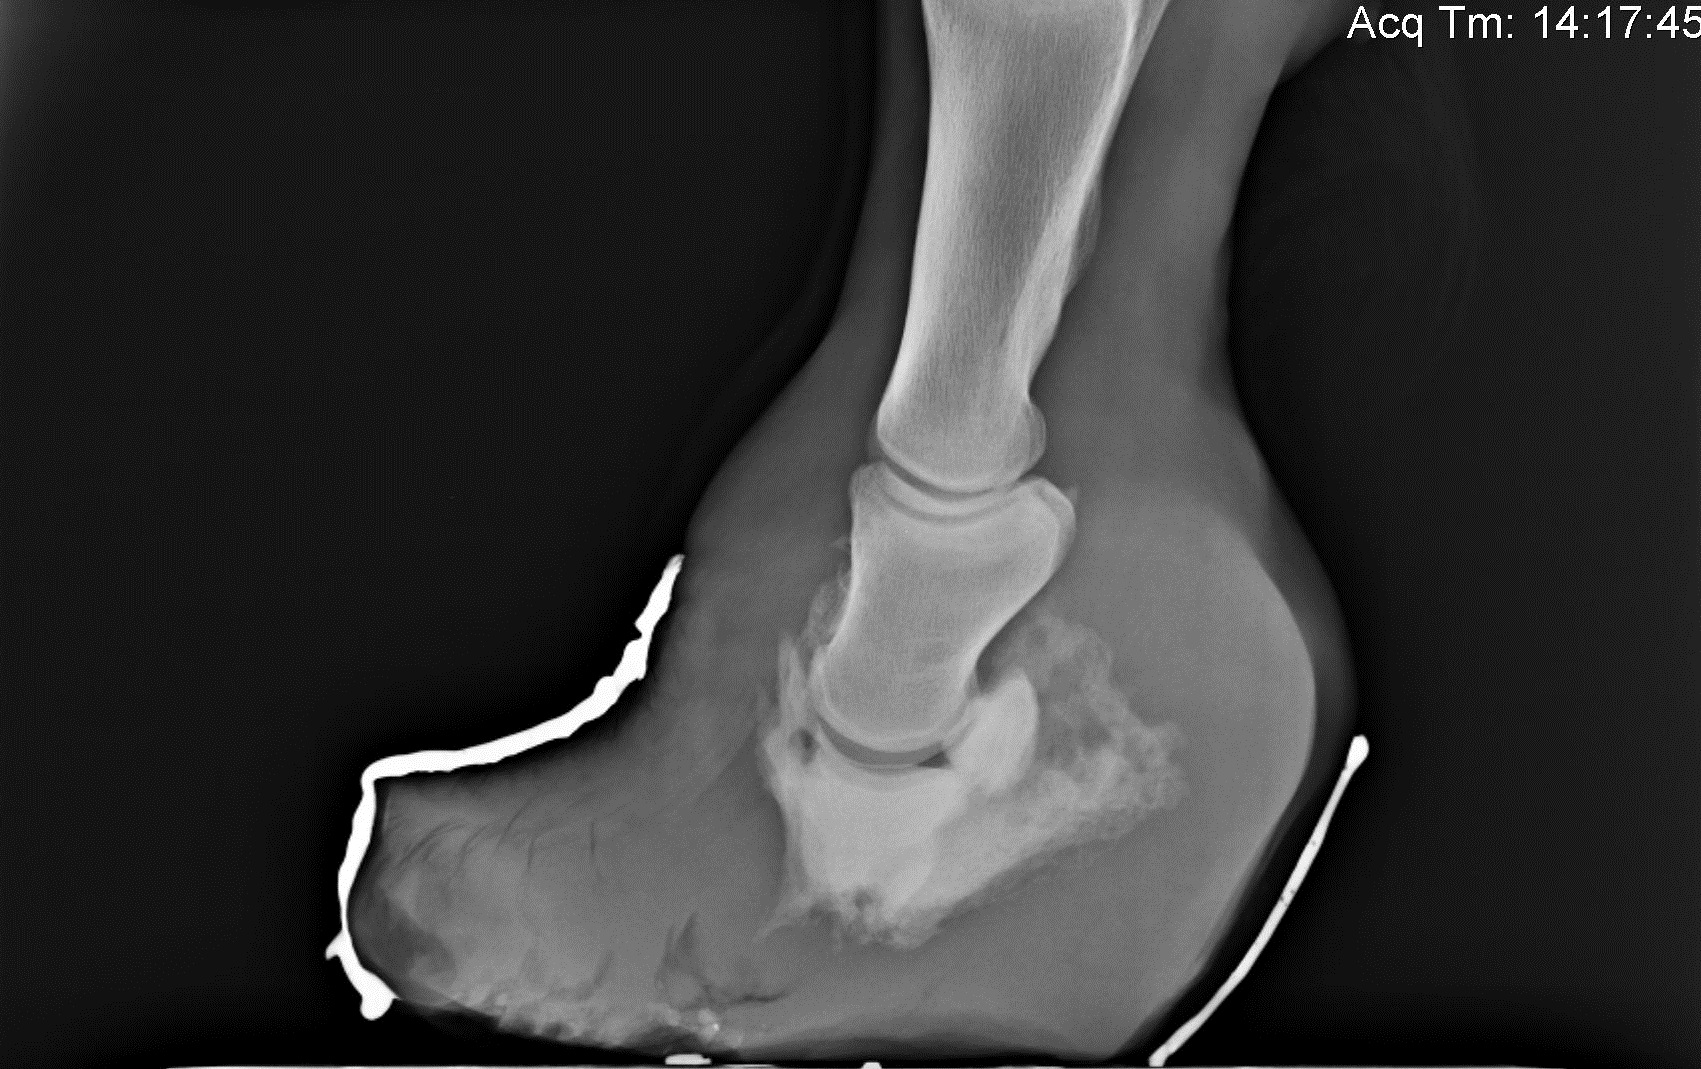

Recognizing the signs of laminitis is extremely important. Affected horses may just seem a little "stiff," or may resent turning sharply left and right. They also may "rock back" onto their hind feet in an attempt to take pressure off the front hooves. Horses suffering from laminitis are identified by observation, physical exam and careful examination of the hooves. Radiographs (x-rays) are incredibly beneficial in making a diagnosis, and the findings can also help with estimating the chance for successful outcome.

Horses with laminitis are treated with a "3-phase" approach. All three phases of treatment are implemented immediately to increase the chance that the horse will return to his career. Phase 1 involves the application of special shoes or pads. We use different types of pads and shoes depending on radiographic (x-ray) findings, but all types center on enhancing the horse's comfort and decreasing further damage. Phase 2 involves the administration of medications. Horses with laminitis usually benefit tremendously from pain control and anti-inflammatories. We also use medications that help with blood flow to the feet in some circumstances. We try to avoid "over-medicating" and resist over-prescribing medications that have no evidence for their use, or that have been proven ineffective. Phase 3 involves dietary management. Since dietary sugars can cause or worsen laminitis, we often recommend limited starch/sugar diets for laminitic horses. Specific recommendations vary from horse-to-horse and we always work with the owner to determine what feeds will be most beneficial.